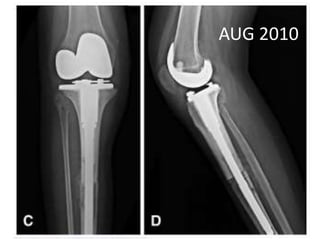

AUG 2010

• MAY 2013 •DENOSUMAB started • 360 mg subcutaneous dose • Followed by 120 mg every month

• 48.

• 49.

• Pain aroundknee joint diminished • Further resection ?? • Patient refused • Clinical improvement persisted until jan 14 • Presented with Rapidly growing painful palpable mass • Open biopsy : high grade sarcoma • A/K amputation